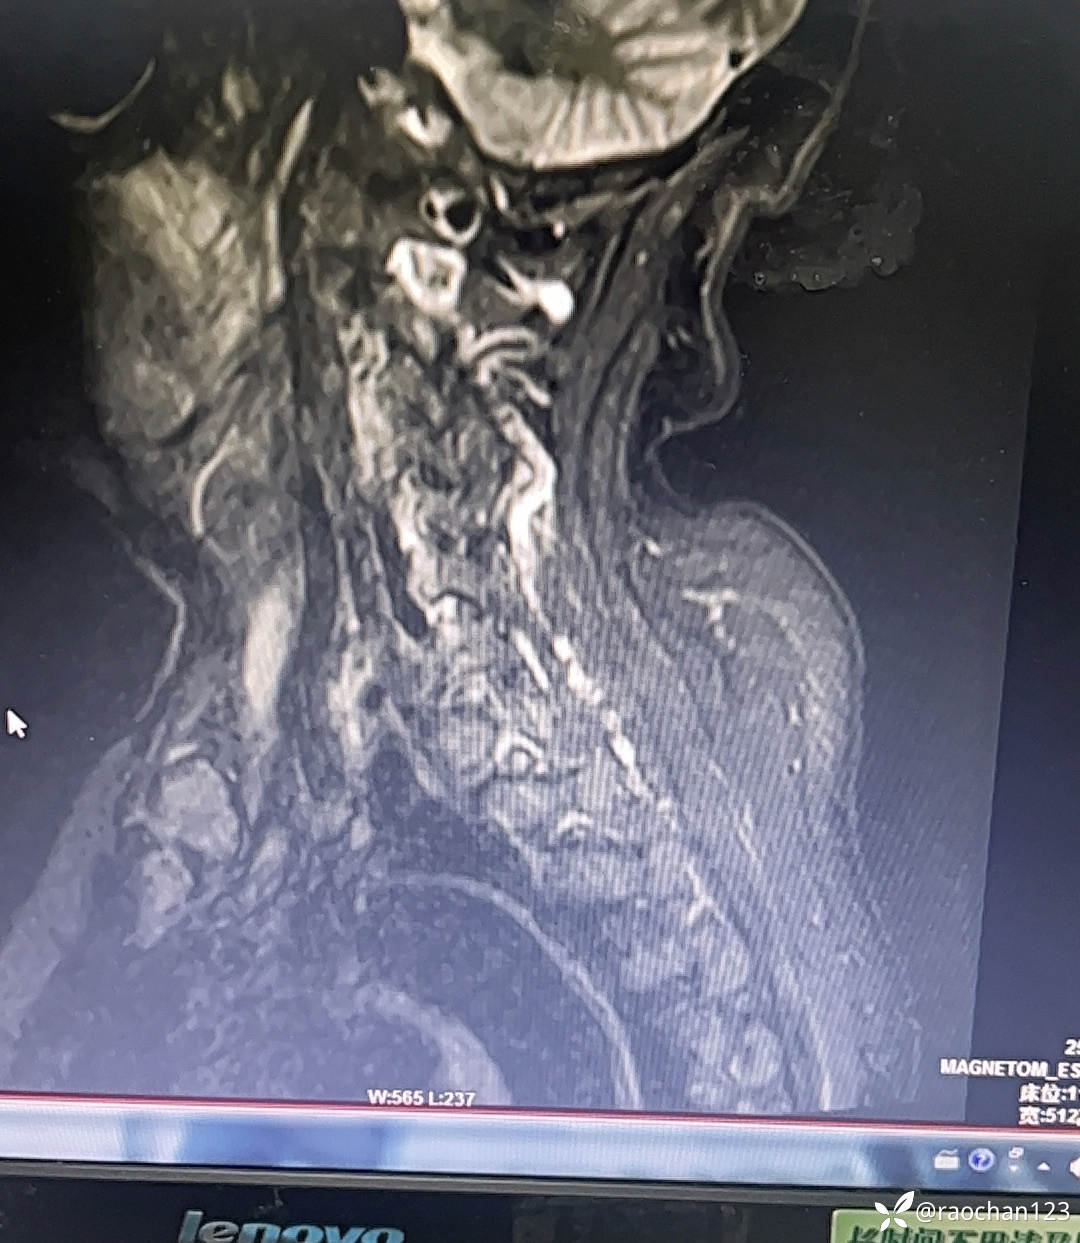

72岁女性,多关节疼痛10日,发热2日,行颈椎MRI示皮下软组织异常信号影,考虑诊断?

类风湿性关节炎?